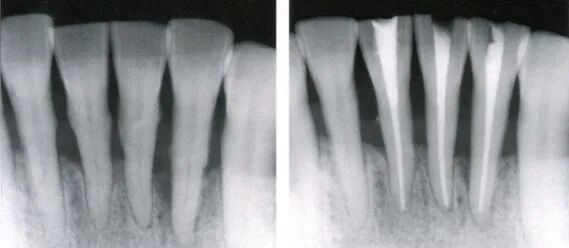

11:根管充填:预先测量主牙胶尖直径并确定工作长度后,2%NaCLO消毒主牙胶尖及辅尖三分钟、无菌纱布擦干。慢弯机螺旋输送器缓慢输送根充糊剂至根管内,将主牙胶尖蘸少量糊剂后缓慢送入根管(确保送至工作长度),侧压器侧压,然后辅尖蘸少量糊剂后送入根管内并再次侧压,依次充填辅尖,直至根管内不能放入多余牙胶尖,将牙胶尖平齐牙冠边缘烫断,拍X片查看根充情况。

12:暂封:X片示根充完好后平齐根管口烫除多余牙胶尖并压实,酒精棉球将窝洞擦拭后暂封(暂封标准同9)。